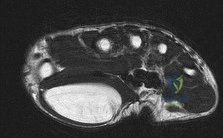

Question 6:

A patient sustains a distal radius fracture and undergoes volar locked plating. Three months postoperatively, she develops an inability to actively extend the interphalangeal joint of her thumb. During exploration, a ruptured tendon is found within the third dorsal extensor compartment. Which of the following bony landmarks does this tendon natively use as a fulcrum?

Options:

- Radial styloid

- Lister's tubercle

- Ulnar styloid

- Scaphoid tubercle

- Pisiform

Correct Answer: Lister's tubercle

Explanation:

The tendon of the Extensor Pollicis Longus (EPL) resides solely within the 3rd dorsal extensor compartment. It uses Lister's tubercle (the dorsal tubercle of the radius) as a fulcrum to angle towards the thumb. EPL rupture is a known complication following both conservative and surgical management of distal radius fractures.